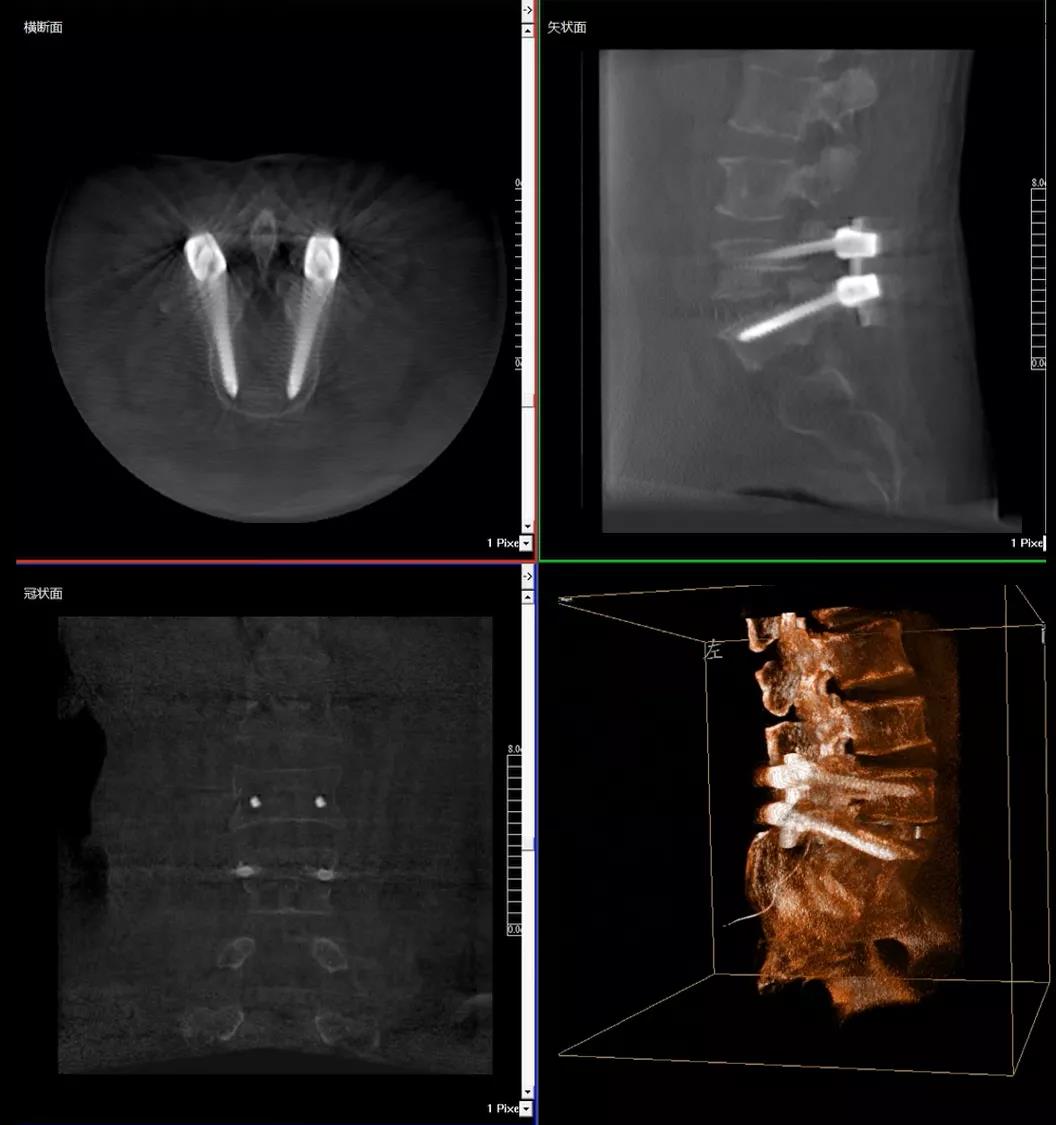

3D C形臂擺位及手術前二維影像

醫生在影像引導下在L5/S1椎弓根處打入醫用螺釘

術中快速生成橫斷面、矢狀面、冠狀面斷層圖像和三維立體圖像